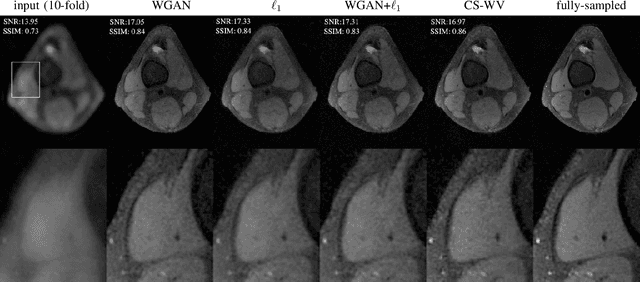

Abstract:Lack of ground-truth MR images (labels) impedes the common supervised training of deep networks for image reconstruction. To cope with this challenge, this paper leverages WGANs for unpaired training of reconstruction networks, where the inputs are the undersampled naively reconstructed images from one dataset, and the outputs are high-quality images from another dataset. The generator network is an unrolled neural network with a cascade of residual blocks and data consistency modules. The discriminator is also a multilayer CNN that plays the role of a critic scoring the quality of reconstructed images. Our extensive experiments with knee MRI datasets demonstrate unpaired WGAN training with minimal supervision is a viable option when there exists insufficient or no fully-sampled training label images that match the input images. Also, supervised paired training with additional WGAN loss achieves better and faster reconstruction compared to wavelet-based compressed sensing.